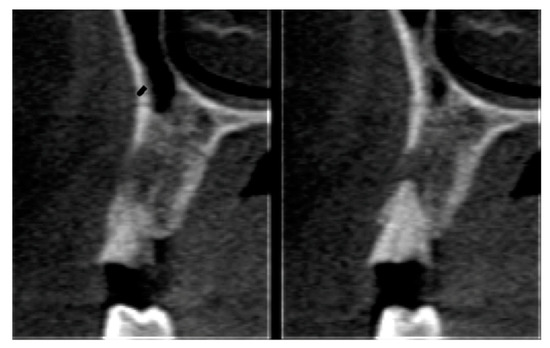

Socket Preservation Using a (Dense) PTFE Barrier with or without Xenograft Material: A Randomized Clinical Trial

2.6. Tomographic Analysis

| Parameter | Before | After | ||

|---|---|---|---|---|

| Mean | Standard Deviation | Mean | Standard Deviation | |

| Buccal plate | 7.37 | 2.32 | 8.49 | 1.95 |

| Socket height | 9.96 | 1.36 | 10.32 | 2.07 |

| Cervical third | 7.68 | 0.94 | 7.57 | 0.92 |

| Medium third | 8.10 | 1.29 | 8.02 | 1.31 |

| Apical third | 8.78 | 1.26 | 8.64 | 1.46 |

| Parameter | Control | Test | P Value | ||

|---|---|---|---|---|---|

| Mean | Standard Deviation | Mean | Standard Deviation | ||

| Buccal plate | 0.46 | 3.04 | 1.11 | 0.91 | 0.417 |

| Socket height | −0.41 | 0.76 | 0.35 | 1.16 | 0.049 |

| Cervical third | −0.89 | 0.71 | −0.11 | 0.73 | 0.008 |

| Medium third | −0.64 | 0.57 | −0.50 | 0.32 | 0.002 |

| Apical third | 0.09 | 0.60 | −0.14 | 0.69 | 0.348 |